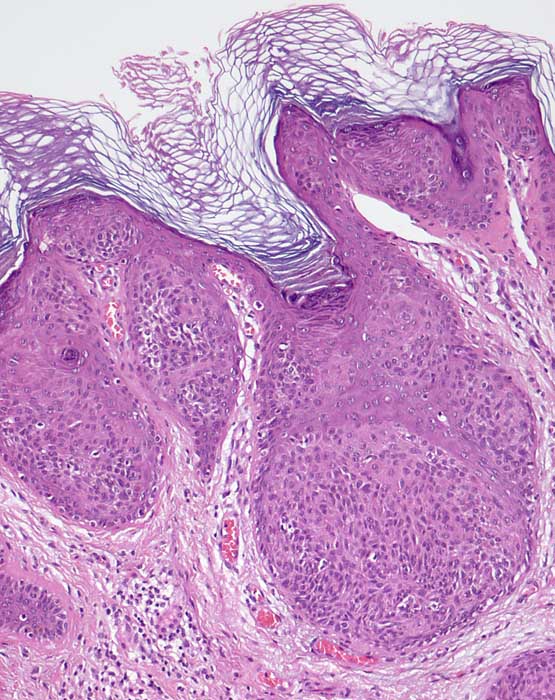

PathoPic – image database / PathoPic ID 7285 - Klonale seborrhoische Warze (Borst Jadassohn Phänomen)

Klonale seborrhoische Warze (Borst Jadassohn Phänomen)

Hyperplastische Epidermis mit umschriebenen Epithelnestern.

Das Borst Jadasshon Phänomen mit intraepidermalen Nestern kann bei verschiedenen Tumorarten auftreten: Hidroacanthoma simplex (intraepidermales Porom), seborrhoische Warze, Morbus Bowen.